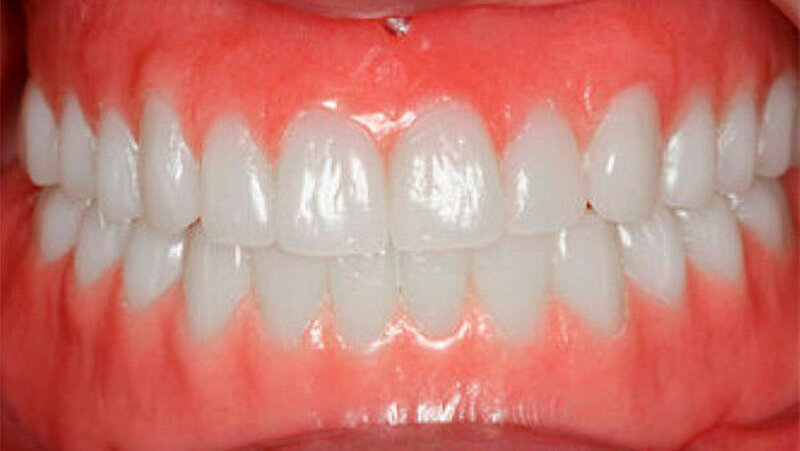

Aufgrund des anatomisch sehr ungünstigen Prothesenlagers war der Erhalt der Restbezahnung im Oberkiefer anzustreben. Nach Kariesexkavation und Wurzelkanalbehandlung konnten beide Zähne mit einer Wurzelstiftkappe versorgt und die alten Prothesen entsprechend umgebaut werden. Im Anschluss an die Meisterabformungen und an die Ausrichtung der Wachswälle wurden die Modelle schädelbezogen einartikuliert, und die Prothesenzähne nach ästhetischen und funktionellen Richtlinien aufgestellt. Eine bilateral balancierte Okklusionsbeziehung konnte umgesetzt werden. Im Oberkiefer wurde eine gerüstverstärkte Totalprothese hergestellt, die auf den beiden Wurzelstiftkappen 16 und 26 verankert war. Im Unterkiefer konnte die Patientin mit einer Totalprothese versorgt werden (Abb. 21 bis 23).

Verbunden mit dem Umstand, dass die Patientin eine ausgeprägte Oligosialie aufweist, ist das Kariesrisiko und hiermit verbunden, auch das Pfeilerzahnrisiko deutlich erhöht. Regelmäßige Kontrolluntersuchungen sind zwingend. Da das Kieferwachstum noch nicht abgeschlossen ist, werden weitere zahnärztliche Behandlungen unumgänglich sein. Diese wenig invasive und relativ zeitnah umsetzbare Therapie erlaubte jedoch eine deutliche Verbesserung der Funktion und der Ästhetik und führte zu einer sichtlichen Stärkung des Selbstbewusstseins. Weitere zukünftige aufwendigere Behandlungsoptionen - insbesondere implantatgetragene Restaurationen - können nun nach abgeschlossenem Wachstum, auf der Basis einer ästhetisch und funktionell akzeptablen Ausgangslage, im Behandlungsteam geplant werden.